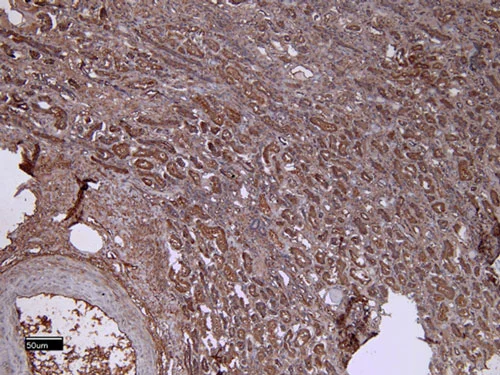

| EB05117 | Goat Anti-ITK Antibody | Pep-ELISA, WB, IF | Human, Mouse | 100µg/200µl |

| EB08802 | Goat Anti-ITK Antibody | Pep-ELISA, WB, IHC, IF, FC | Human, Rat, Cow | 100µg/200µl |